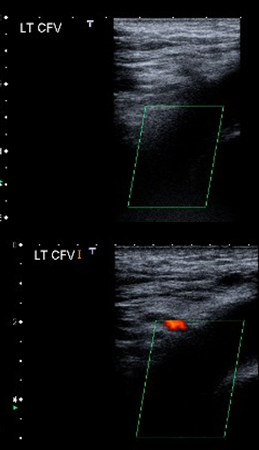

Exploración ecográfica con doppler a color que muestra el trombo de la vena femoral común izquierda.